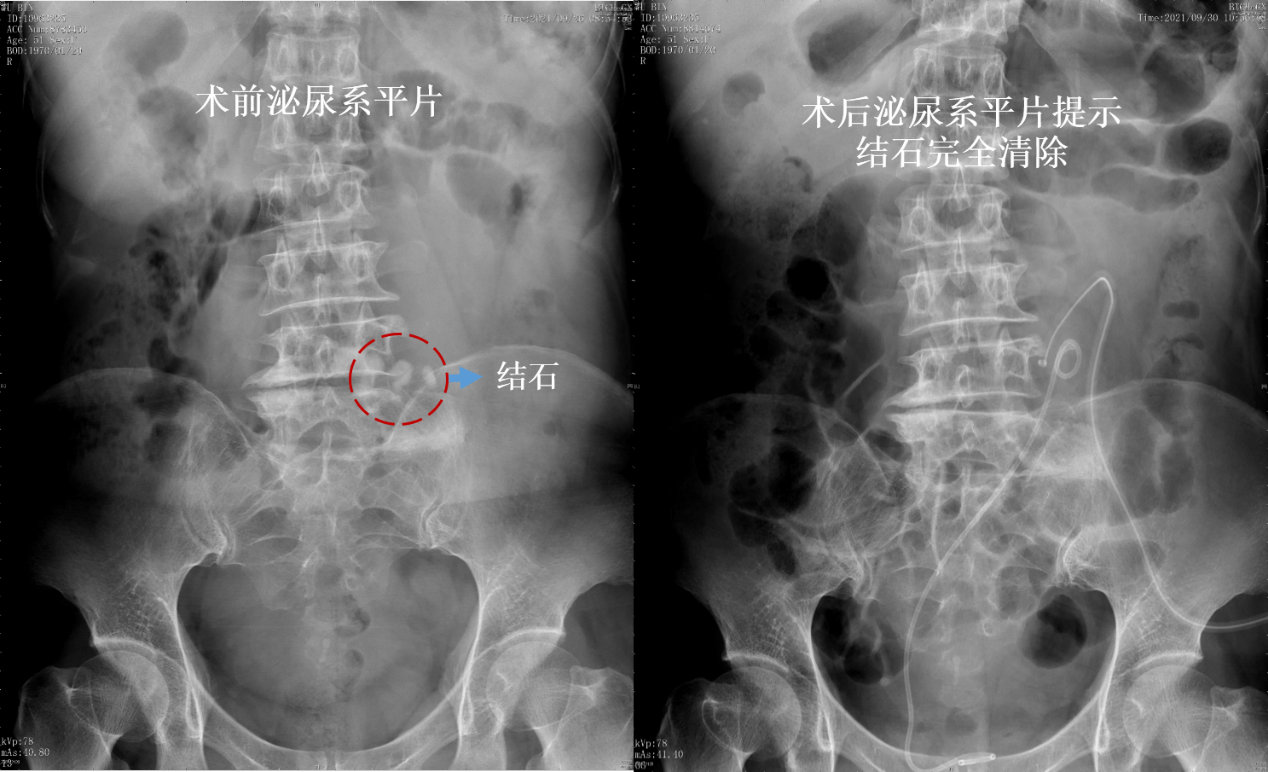

术前(左)、术后(右)影像对比

术后,张女士恢复顺利,第1天就能够顺利排气,下地活动。复查X线和CT显示,不仅结石完全被清除,而且脏器保护良好,没有出现腹腔内脏器和血管损伤,腹腔内积液、尿漏等手术并发症等。10天后,张女士顺利出院。(编辑 于悦超)